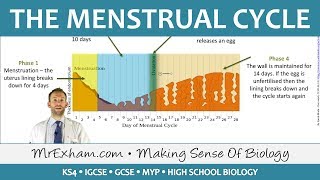

44. Animal Reproduction

Animal Reproduction

Menstrual Cycle (Mnemonic)